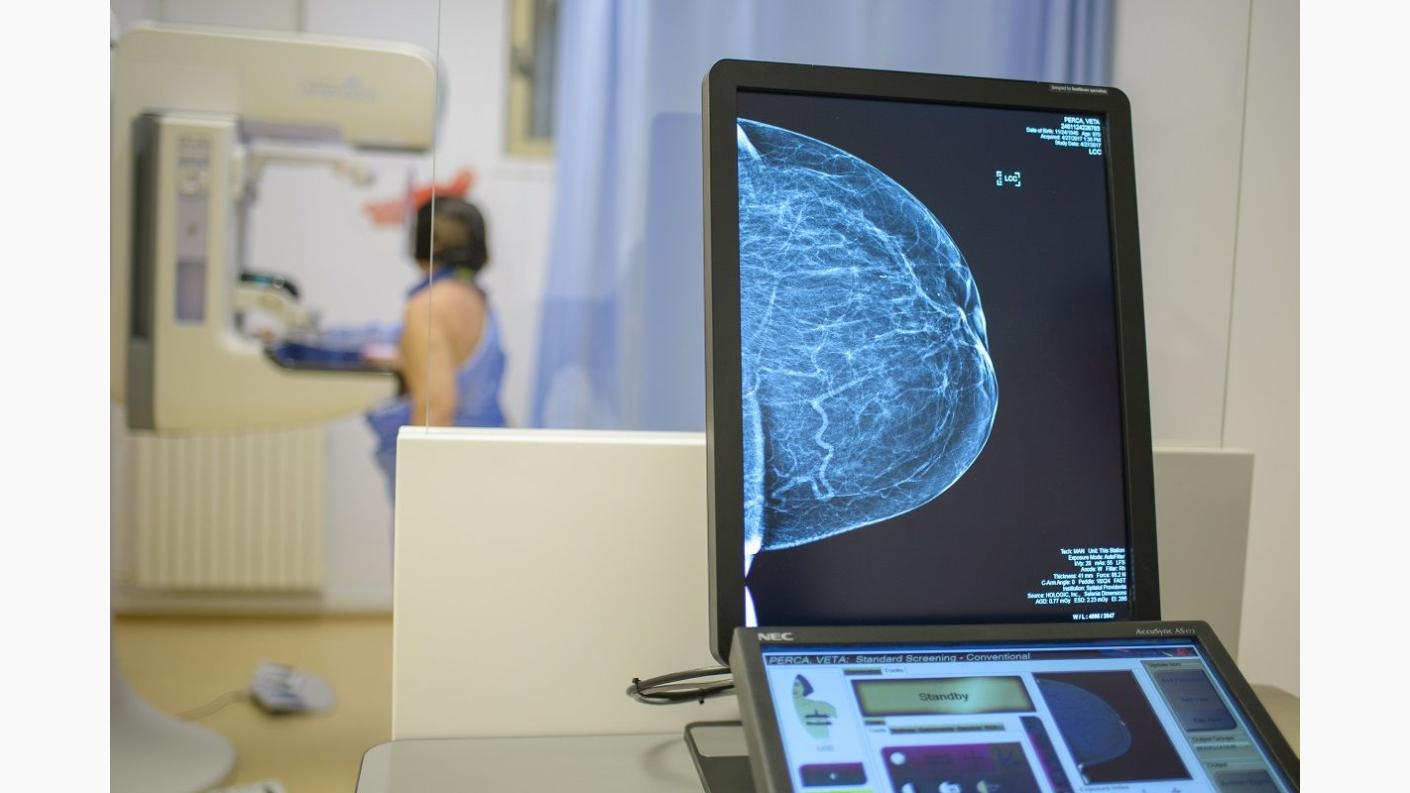

În perioada 01 – 31 octombrie 2017, Spitalul „Providenţa” a desfăşurat campania „Depistat la timp, îl putem învinge împreună!” în cadrul căreia 70 de femei au optat pentru efectuarea investigaţiilor mamografice şi/sau ecografice pentru diagnosticarea din timp a afecţiunilor glandei mamare.

Având în vedere adresabilitatea mare şi creşterea alarmantă a numărului de cazuri care sunt diagnosticate cu cancer de sân, Spitalul „Providenţa” va prelungi campania de reduceri până la data de 15 decembrie 2017. Astfel, până la data stabilită se va menţine reducerea de 20% pentru toate tipurile de investigaţii mamografice (mamografie digitală 2D, mamografie digitală cu tomosinteză (3D), mamografie 2D+3D).

Prin intermediul campaniei „Depistat la timp, îl putem învinge împreună!” desfăşurată în cadrul „Centrului de examinare și diagnosticare în patologia glandei mamare”, Spitalul „Providența” se alătură organizațiilor care desfășoară campanii de conștientizare şi de luptă împotriva cancerului de sân.